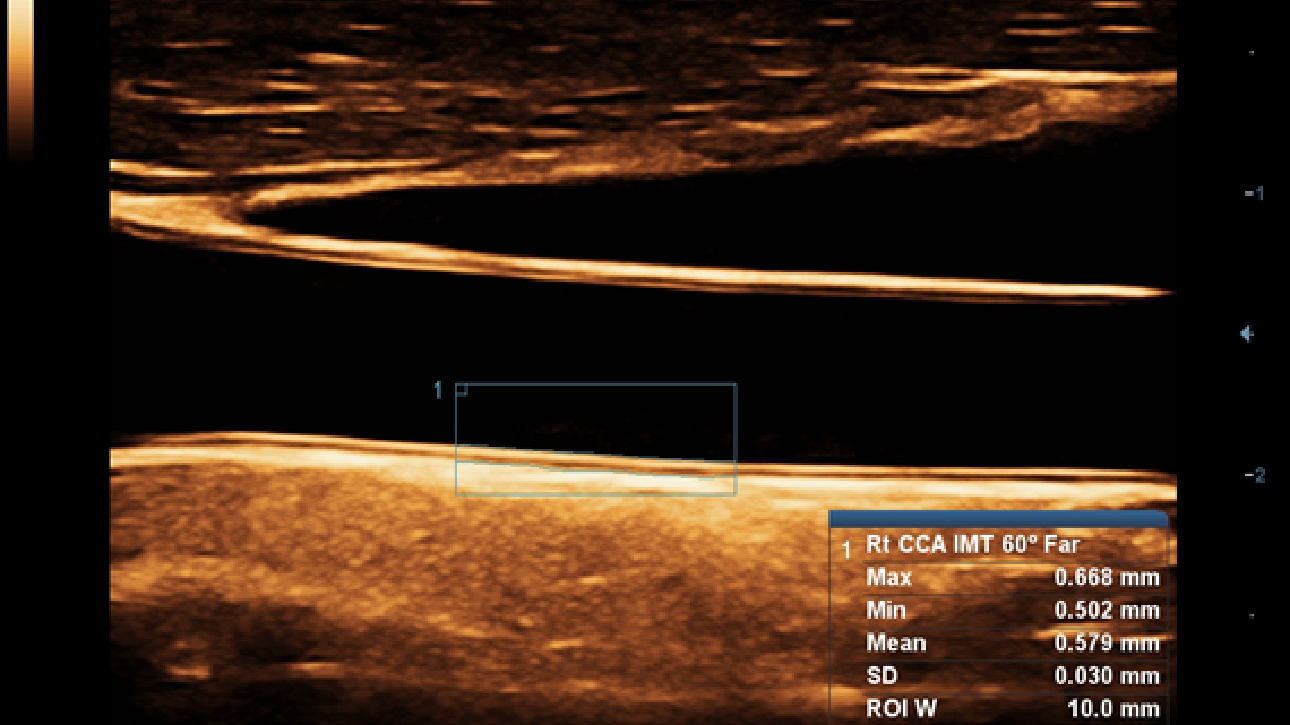

Als allround partner zet DC-60 Exp met X-Insight zich in om een allesomvattende oplossing te zoeken waarmee u alle aspecten van uw dagelijkse klinische activiteiten gemakkelijk en trefzeker kunt beheren.

De DC-60 Exp met X-Insight is ontworpen op basis van diepgaand inzicht in klantbehoeften om hoge effici?ntie met nauwkeurige beeldverwerking te leveren, dankzij eXacte helderheid, eXceptionele intelligentie en eXcellente ervaring.

Uiterst productieve ervaring